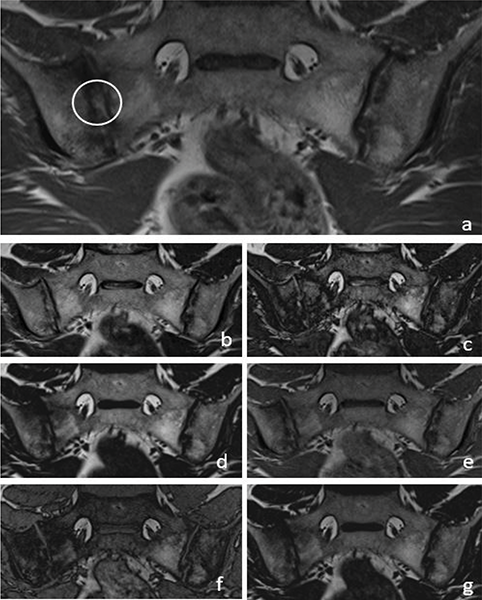

Figure 4

A 36‑year‑old male patient with backfill (circle) in the right sacroiliac joint on a T1W images (a). T2W Dixon IP (b), T2W Dixon OP (c), T2W Dixon FO (d), T1W Dixon IP (e), T1W Dixon OP (f) and T1W Dixon FO (g) images are also shown in the figure.